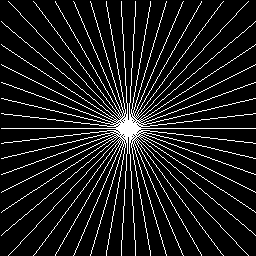

Refer to caption

(a) 10%

(b) 20%

(c) 30%

(d) 40%

Figure 7: Radial sampling masks used in our experiments.

We used two sets of MR images from the IXI database444\urlhttp://brain-development.org/ixi-dataset/ (the brain dataset) and from the Data Science Bowl challenge 555\urlhttps://www.kaggle.com/c/second-annual-data-science-bowl/data (the chest dataset) to assess the performance of our method by comparing our results with state-of-the-art CS-MRI methods (e.g., Convolutional sparse coding-based [20, 21], patch-based dictionary [19, 37, 18], deep learning-based [26, 24, 25, 27], and GAN-based [33, 32]). The image resolution of each image is 256x256. From each database, we randomly selected 100 images for training the network and another 100 images for testing (validating) the result. We conducted the experiments for various sampling rates (i.e., 10%, 20%, 30%, and 40% of the original k𝑘k-space data), corresponding to 10×\times, 5×\times, 3.3×\times, and 2.5×\times factors of acceleration. We assume the target MRI data type is static, and radial sampling masks are applied (Figure 7). It is worth noting that our experimental data are real-valued MRI images, which require pre-processing of the actual acquisition from the MRI scanner because the actual MRI data is complex-valued. Additional data preparation steps, such as data range normalization and imaginary channel concatenation, are also required.